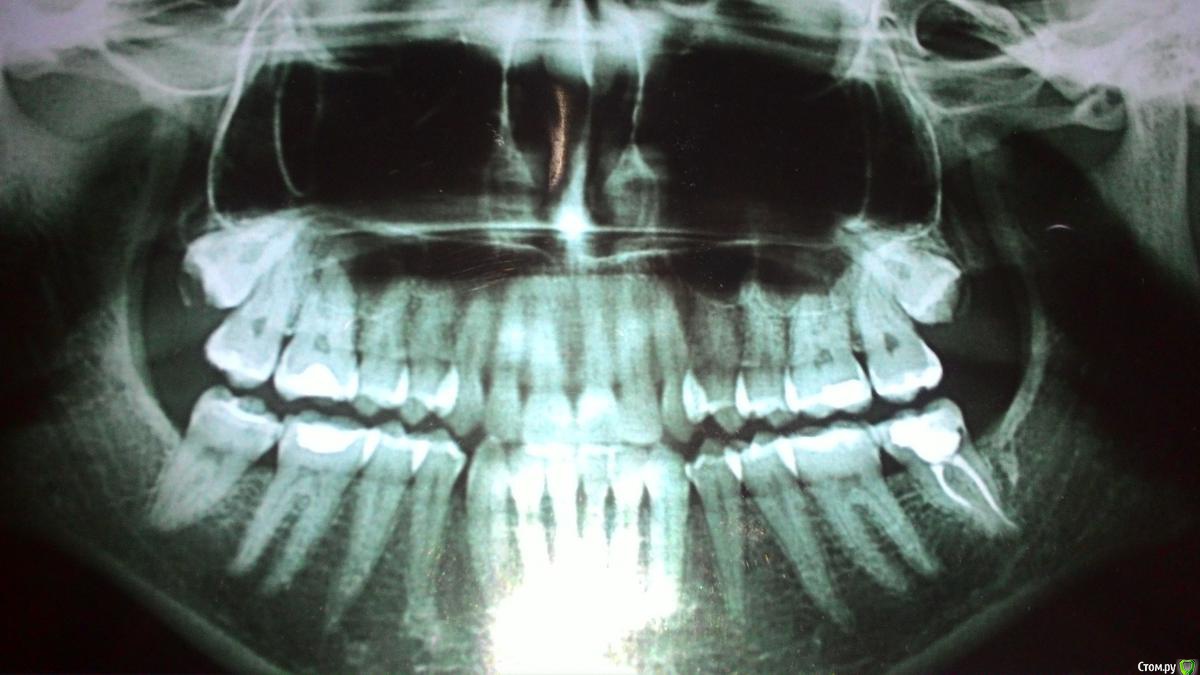

MargaritaM Опубликовано 29 октября, 2016 Поделиться Опубликовано 29 октября, 2016 Здравствуйте! Помогите, пожалуйста, советом, куда идти и что делать. С декабря 2013 года наблюдаюсь на Вучетича у профессора-хирурга (ЧЛХ). Диагноз: ретинированные верхние восьмерки, правая с зубосодержащей кистой. Хирург отказывается удалять, так как не видит хирургических причин удалять. На тему кисты говорит, что ничего страшного, если не растет - с ней можно всю жизнь проходить. Также не хочет удалять, т.к. с высокой вероятностью будет свищ, перфорация в пазуху. Делали ЭОД, хирург указал, что ноющая боль вызвана правой верхней шестеркой. Терапевт говорила, что всё с ней хорошо, но так как года 3 постоянно на нее жаловалась, удалили нерв. Удаление произошло не без приключений: заложили девитпасту на неделю, через 3 дня после заложения пасты адская боль, ее коллега удалила нерв (гноя, запаха не было, нерв не "рвался"), боль держалась, оставили зуб без пломбы на 2 дня, потом закладывали лекарство еще на 2 дня и прописали антибиотики. Боль постепенно стихала, но держалась. Дырку заделали пломбой. Сделали снимок - все каналы заделаны хорошо. После постановки пломбы зуб ныл около 2х недель. До сих пор периодичеки шестерка ныла, особенно когда простужалась или сильно нервничала. Сейчас есть как 4й день ноющая нестихающая боль в области между правой восьмеркой и шестеркой, с усилением ближе к ночи. Первые 3 дня ныла незначительно, сейчас уже сильнее. Есть ощущение, что десна немного припухла, цвет розовый, как у десны около других зубов. Подскажите, пожалуйста, шаг действий и куда еще можно обратиться на тему консультации с дальнейшим лечением/удалением.Пока записалась на прием к другому стоматологу-терапевту на консультацию на 2 ноября. Но сегодня 29 октября, как бы за 4 суток не стало поздно Ссылка на комментарий

kramer Опубликовано 29 октября, 2016 Поделиться Опубликовано 29 октября, 2016 Я бы удалил обе 8ки. Риск перфорации есть всегда, но это управляемо - можно же пластику сделать, ушить. Далее разбираться с 6 зубом. 1 Ссылка на комментарий

kladoffka Опубликовано 30 октября, 2016 Поделиться Опубликовано 30 октября, 2016 Вообще сложностей не увидел в обоих зубах. 2 Ссылка на комментарий

Kazankov.Egor Опубликовано 30 октября, 2016 Поделиться Опубликовано 30 октября, 2016 Кт верхней челюсти сделать нужно, сложности в удалении зубов нет, перфорация верхнечелюстной пазухи - рутинная амбулаторная процедура, решается за 20 минут.Не понятно что будет искать ЛОР. Ссылка на комментарий